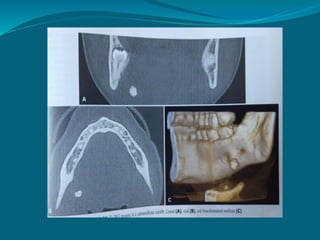

CBCT imaging

 Useful for evaluating structures in & adjacent to

salivary gland

 Cannot resolve soft tissue densities.

 Minimal calcified sialolith well depicted.

 Three D visualization possible.

CBCT SIALOGRAPHY IMAGING

 3D reconstruction can be performed and the ductal

architecture viewed in all possible dimensions.

 Information about measurements and location of

sialoliths.

 Highly reliable technique for identifying both

radiopaque as well as radiolucent sialoliths and ductal

strictures.

 Less exposure dose and cost effective.

Lateral and axial view